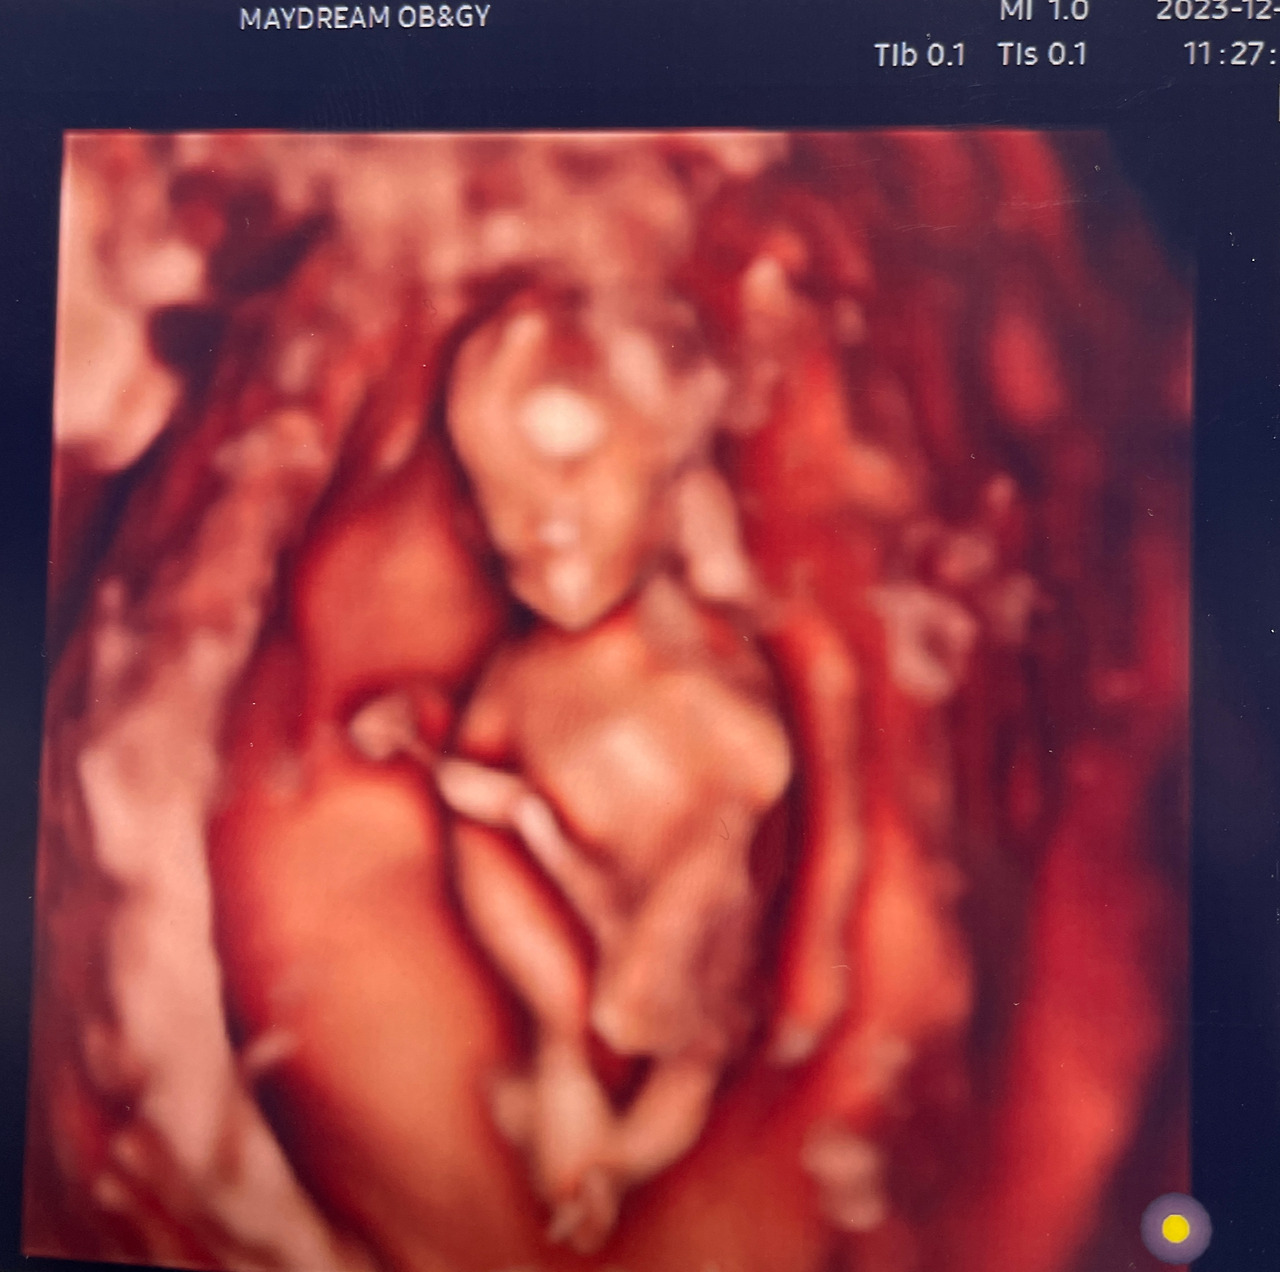

그나저나 네가 생긴 지 벌써 14주라니. 시간이 얼마나 빠른지 모르겠어. 임신 극초기 때는 하루하루가 그렇게 가지 않더니 지금은 일주일이 쏜살같이 지나가는구나. 너의 성장을 알려주는 어플이 차오르는 너의 주수를 알려줄 때마다 정말 신기하고 놀라울 따름이야. 이제 너는 거의 완전한 사람의 형태를 갖추어 눈코입은 물론 손가락 발가락도 있고, 손가락을 빨거나 기지개를 켜기도 한단다. 피부도 점점 두꺼워지고 있다는구나. 혼자서 열심히 스스로에게 필요한 걸 만들어가는 너를 보며 경이로운 기분이 든다. 정말 고마워 미르야.

KakaoTalk_20240119_143358931.jpg 알아서 잘 자라고 있는 너

임신 14주│태반이 거의 완성되어 자궁에 뿌리를 내리는 시기. 태아는 피부가 두꺼워지고 불투명해지면서 내장을 보호하게 되며, 생식기가 외부로 드러나기 시작한다. 태아의 크기는 8.7cm 내외로 복숭아 크기!